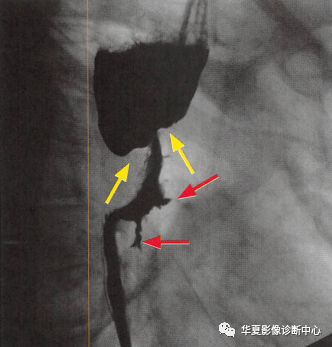

食管癌在鋇餐造影下的一種表現(xiàn)之一,顯示食管局部不規(guī)則狹窄(黃箭頭:玫瑰花花干),近端食管擴(kuò)張(萎陷的玫瑰花朵),兩個(gè)不規(guī)則線狀潰瘍(紅箭頭:玫瑰花葉/刺),形似黑色玫瑰花,小編原創(chuàng)命名為:“黑色玫瑰花征”,幫助記憶,加深映像